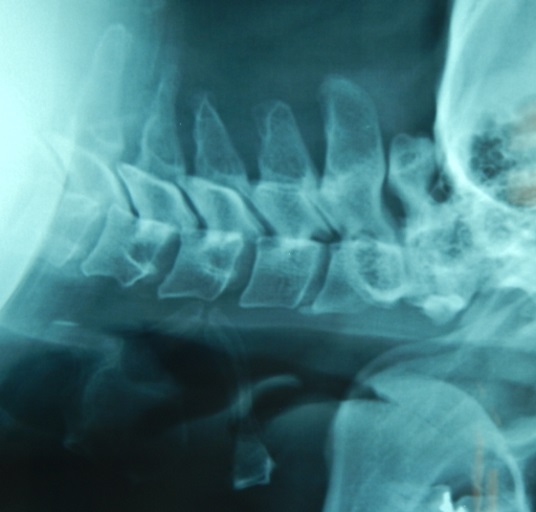

Start with getting cervical spine x-rays, because this helps to diagnose atlantoaxial instability.

So you will need to get flexion extension views in patients with rheumatoid arthritis, especially preoperative x-rays, and if it looks bad, you have to stabilize the spine before doing elective total hip or total knee procedures.

You see in the x-rays the Atlanto Dental Interval: A.D.I., if it was more than 3.5 mm that means instability of the upper cervical spine may be present.

If it is more than 7 mm it means disruption of the alar ligament, these patients can have cervical spine myelopathy.

The A.D.I. is an unreliable predictor of paralysis.

The posterior atlanto dental interval is a better predicting test, it can predict the spinal cord injury better.

If the posterior A.D.I. is less than 14 mm it can predict spinal cord injury, get an MRI.

The surgery is done if the A.D.I. is more than 10mm or if the P.A.D.I. is less than 14mm, the operation is C1-C2 fusion.